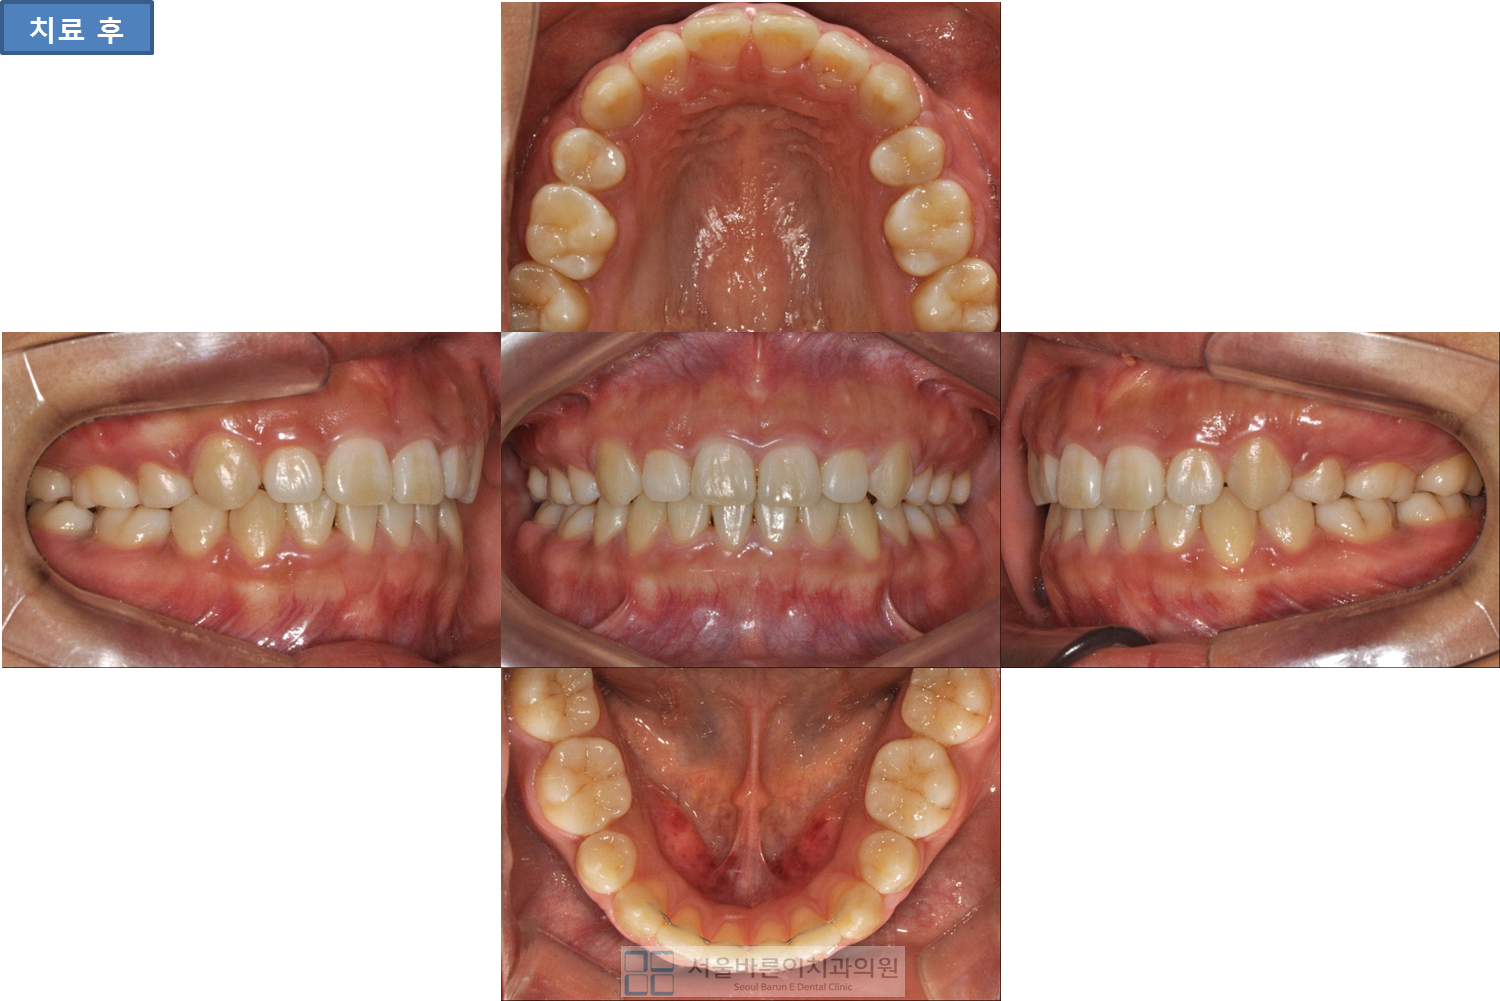

![]() ![]() 개방교합과 돌출입때문에 교정치료를 받으신 분이십니다. 4개의 소구치를 발치하여 돌출입과 개방교합을 해결하였습니다. 당신의 미소를 생각합니다, 교정전문 서울바른이치과 |